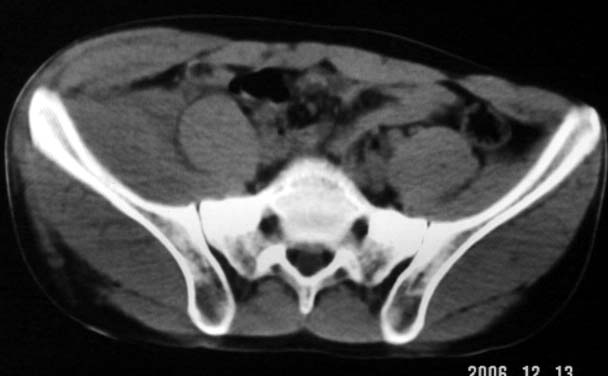

以下是引用守望可可西里在2006-12-13 22:25:00的发言:[br]再明确不过的右侧髂骨骨折,呵呵,这回总不会被忽悠了!

以下是引用liuyue在2006-12-13 23:45:00的发言:[br]右侧髂骨骨折伴局部软组织及腹壁肿胀

以下是引用xiaoniu在2006-12-13 22:22:00的发言:[br]右侧髂前上嵴骨折伴局部腹壁血肿。[br][br][本贴已被 xiaoniu 于 2006-12-13 22:24:13 修改过]